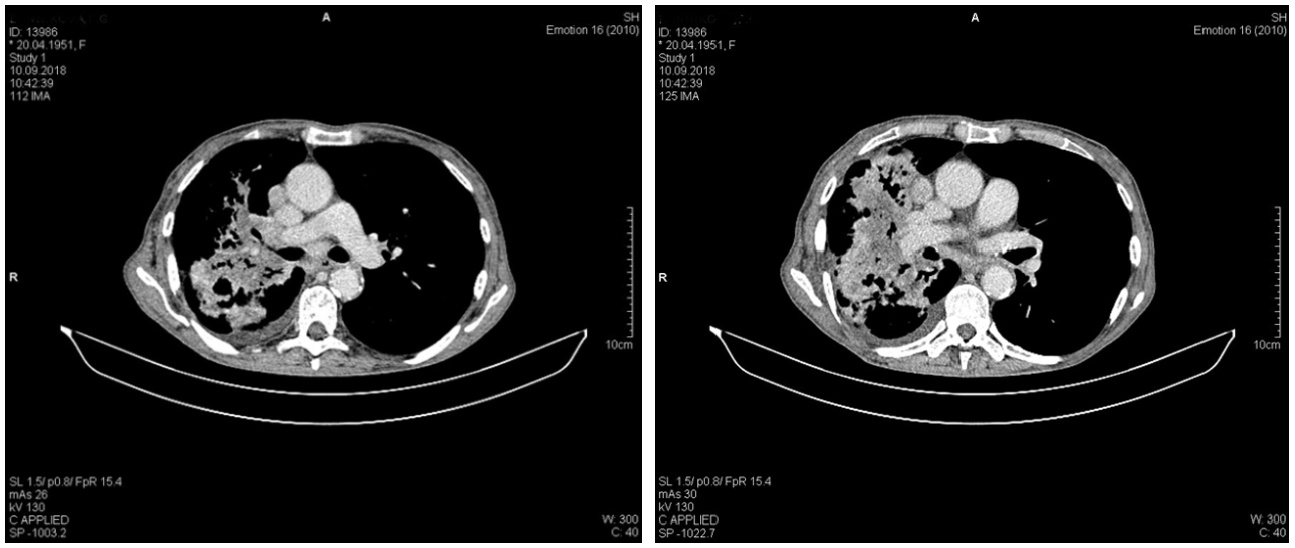

Дообследована с помощью компьютерной томографии органов грудной клетки 18.11.2018 (рис. 4). В плевральной полости справа определяется большое количество жидкости, сепарация листков до 100 мм. Пневматизация правого легкого значительно снижена. В S1-2 левого легкого перисциссурально отмечается появление неправильной формы инфильтрата, с неровными контурами, неоднородного по структуре, размерами до 27 мм. В апикальных отделах S1-2, в S8 левого легкого визуализируются участки локального тяжистого пневмофиброза. Легочной рисунок левого легкого деформирован за счет пневмосклероза, явлений центролобулярной эмфиземы. Определяются многочисленные увеличенные (до 25 мм) внутригрудные лимфоузлы.

Рис. 4. Компьютерная томография органов грудной клетки от 18.11.2018